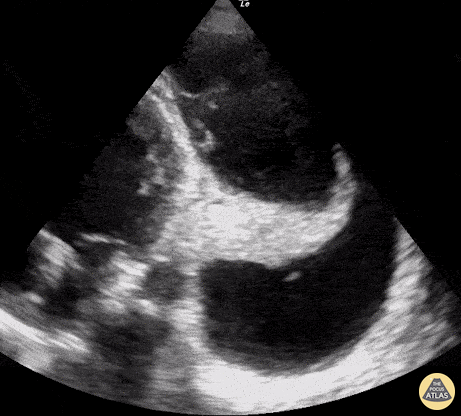

Seen here is an unexpected finding while acquiring an apical 4 chamber view with a phased array probe. The four chambers of the heart are difficult to bring into view due to the presence of large left pleural effusion with ipsilateral collapsed lung floating within the pleural fluid. This visual of atelectatic lung swimming within a pleural effusion is referred to as “jellyfish sign”. Renato Tambelli, Emergency Physician Hospital das Clínicas de Marília, Brazil. @R_Tambelli // @JediPocus